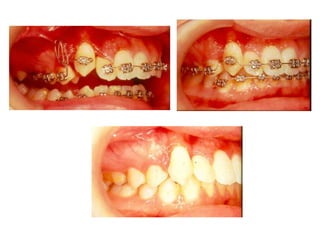

TRANSPOSIÇÃO TOTAL - CANINO COM INCISIVO LATERAL MANOBRAS PARA CORREÇÃO DA ROTA DE ERUPÇÃO